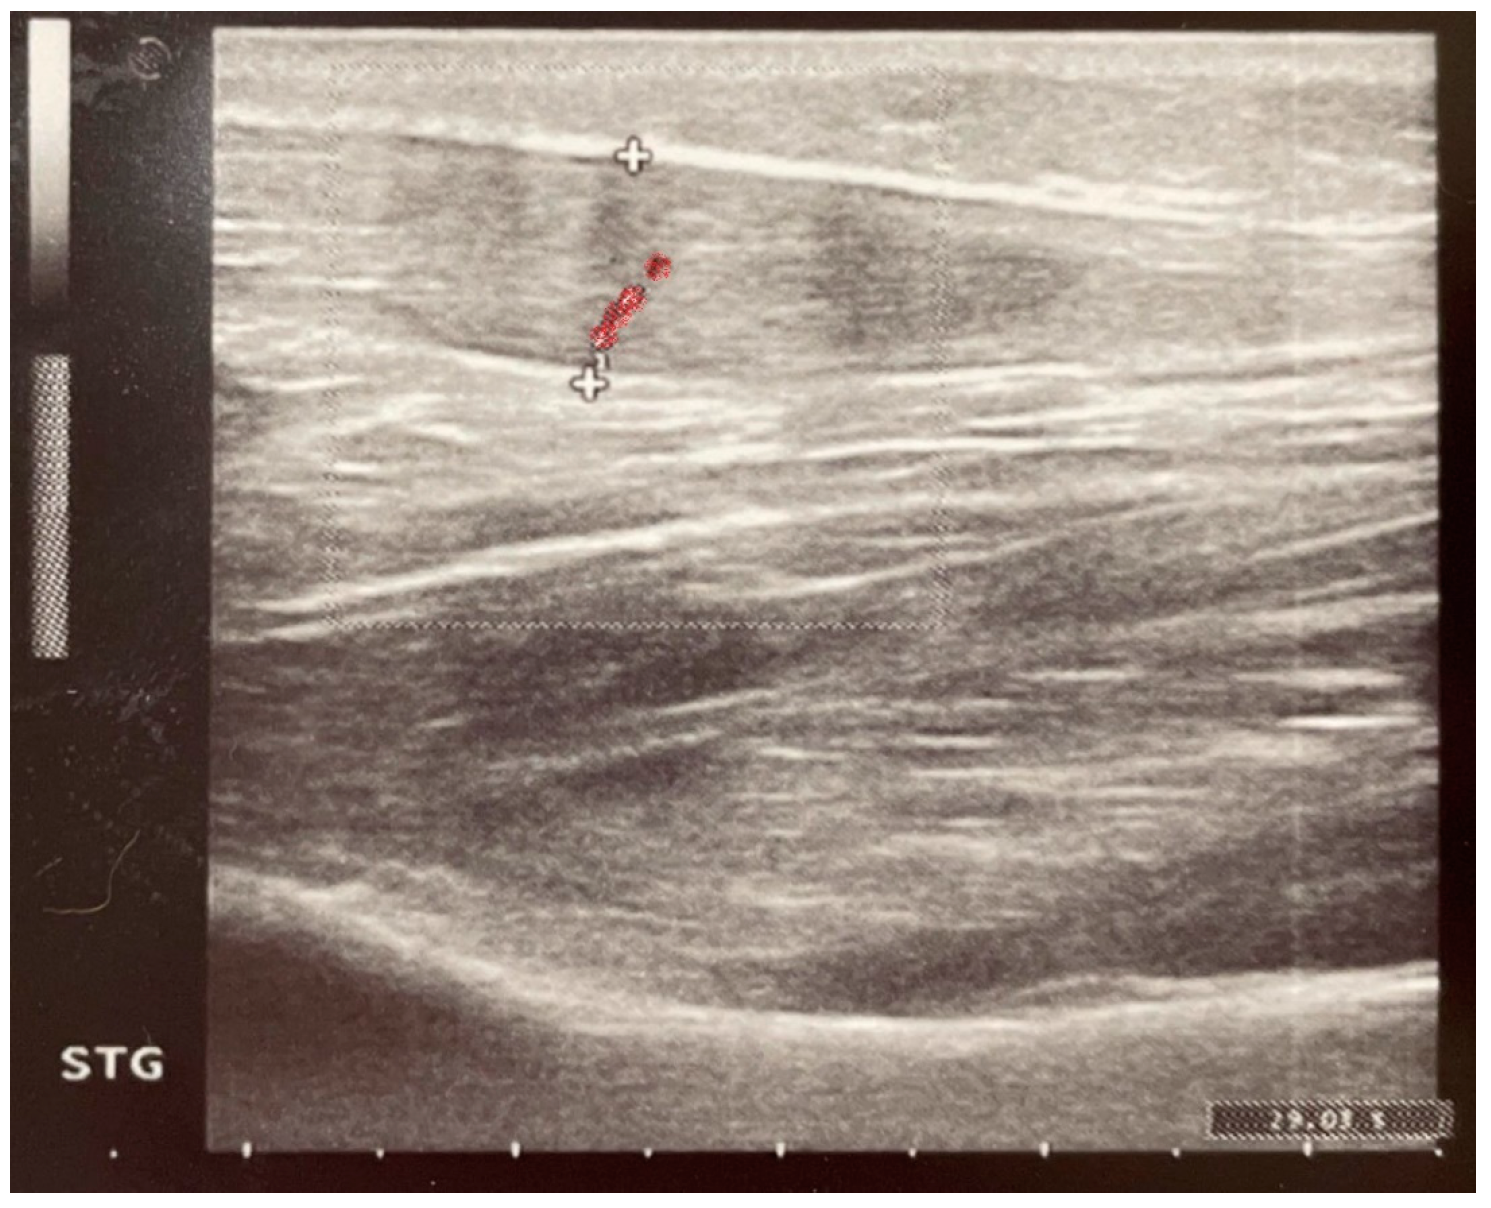

2.4. Paraclinical Evaluation—Ultrasound

| Achilles Tendon Thickness (Left Leg) [mm] | Achilles Tendon Thickness (Right Leg) [mm] | |

|---|---|---|

| Induction | ||

| Group C | 4.327 ± 0.502 | 4.313 ± 0.4389 |

| Group ES | 4.500 ± 0.5907 | 4.480 ± 0.3676 |

| Day 8 | ||

| Group C | 5.173 ± 1.529 | 4.693 ± 0.7488 |

| Group ES | 5.470 ± 1.105 | 5.170 ± 0.7439 |

| 3 Months | ||

| Group C | 5.100 ± 1.144 | 5.100 ± 1.313 |

| Group ES | 5.830 ± 1.643 | 5.310 ± 0.7340 |